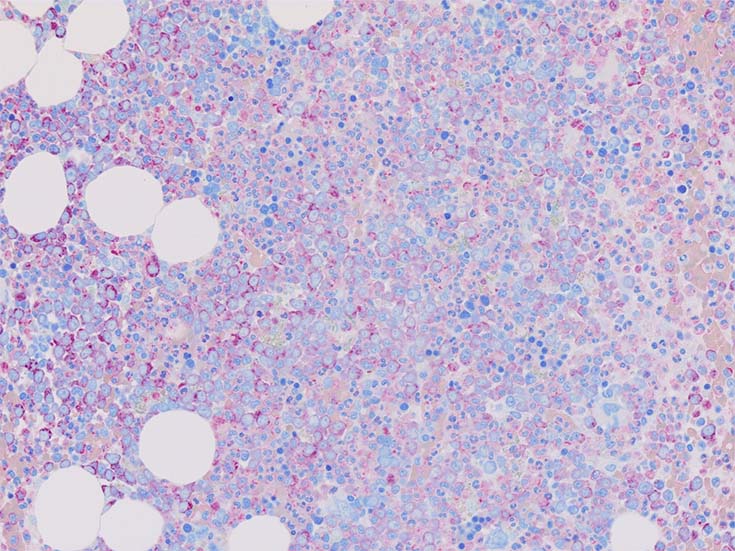

初診時の骨髄組織所見

HE染色および, Naphtol-ASD-CAE染色した骨髄クロット組織標本-->Naphtol-ASD-CAE染色, 載せガラス法のページをみる.

70-80%のhypercellular marrow. 3系統造血細胞が認められる. Naphtol-ASD-CAE染色で赤色にそまる顆粒球系細胞増生が顕著な骨髄組織.

promyelocytesなど幼若顆粒球系細胞の集簇がみられるが, 分葉好中球他, 成熟顆粒球(Naphtol-ASD-CAE染色は薄く染まる傾向あり)も多く認められacute leukaemiaの所見ではない.

単球(Naphtol-ASD-CAE染色陰性)が密に増殖する所見は骨髄組織には認められない(*1)